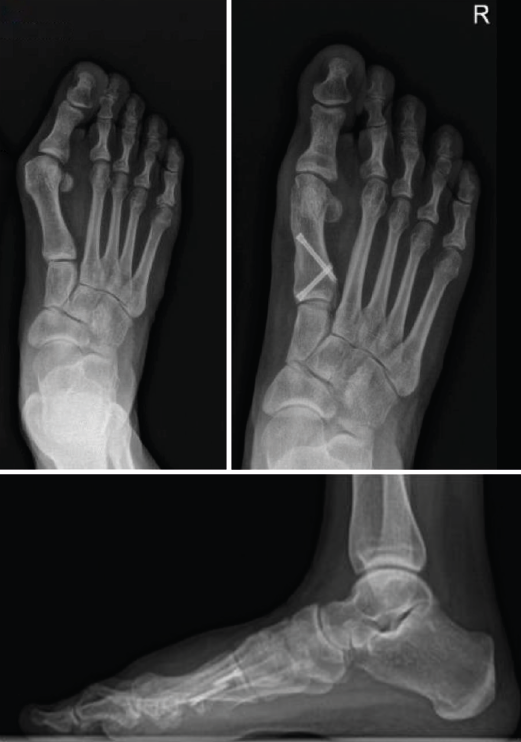

Figura 5. Caso clínico de osteotomía de cierre (radiología preoperatoria y control a los 4 años).

En las Figuras 4 y 5 se muestra un ejemplo intervenido de osteotomía de apertura y cierre.

Se han realizado 22 osteotomías proximales (15 de apertura y 7 de cierre). La puntuación de la AOFAS preoperatoria de estos pacientes era de 54, aumentando a 92 en el control realizado en el momento de la revisión (6 años y 8 meses de media); esto supone un incremento del 70%. Radiográficamente, el ángulo intermetatarsiano prequirúrgico medio era de 19° y el posquirúrgico medio era de 11,7°; por tanto, una corrección media de 7,3°. Además, ha existido un alargamiento del metatarsiano de 3 mm en las osteotomías de apertura y una disminución de 6 mm en las osteotomías de cierre (Tabla 2).